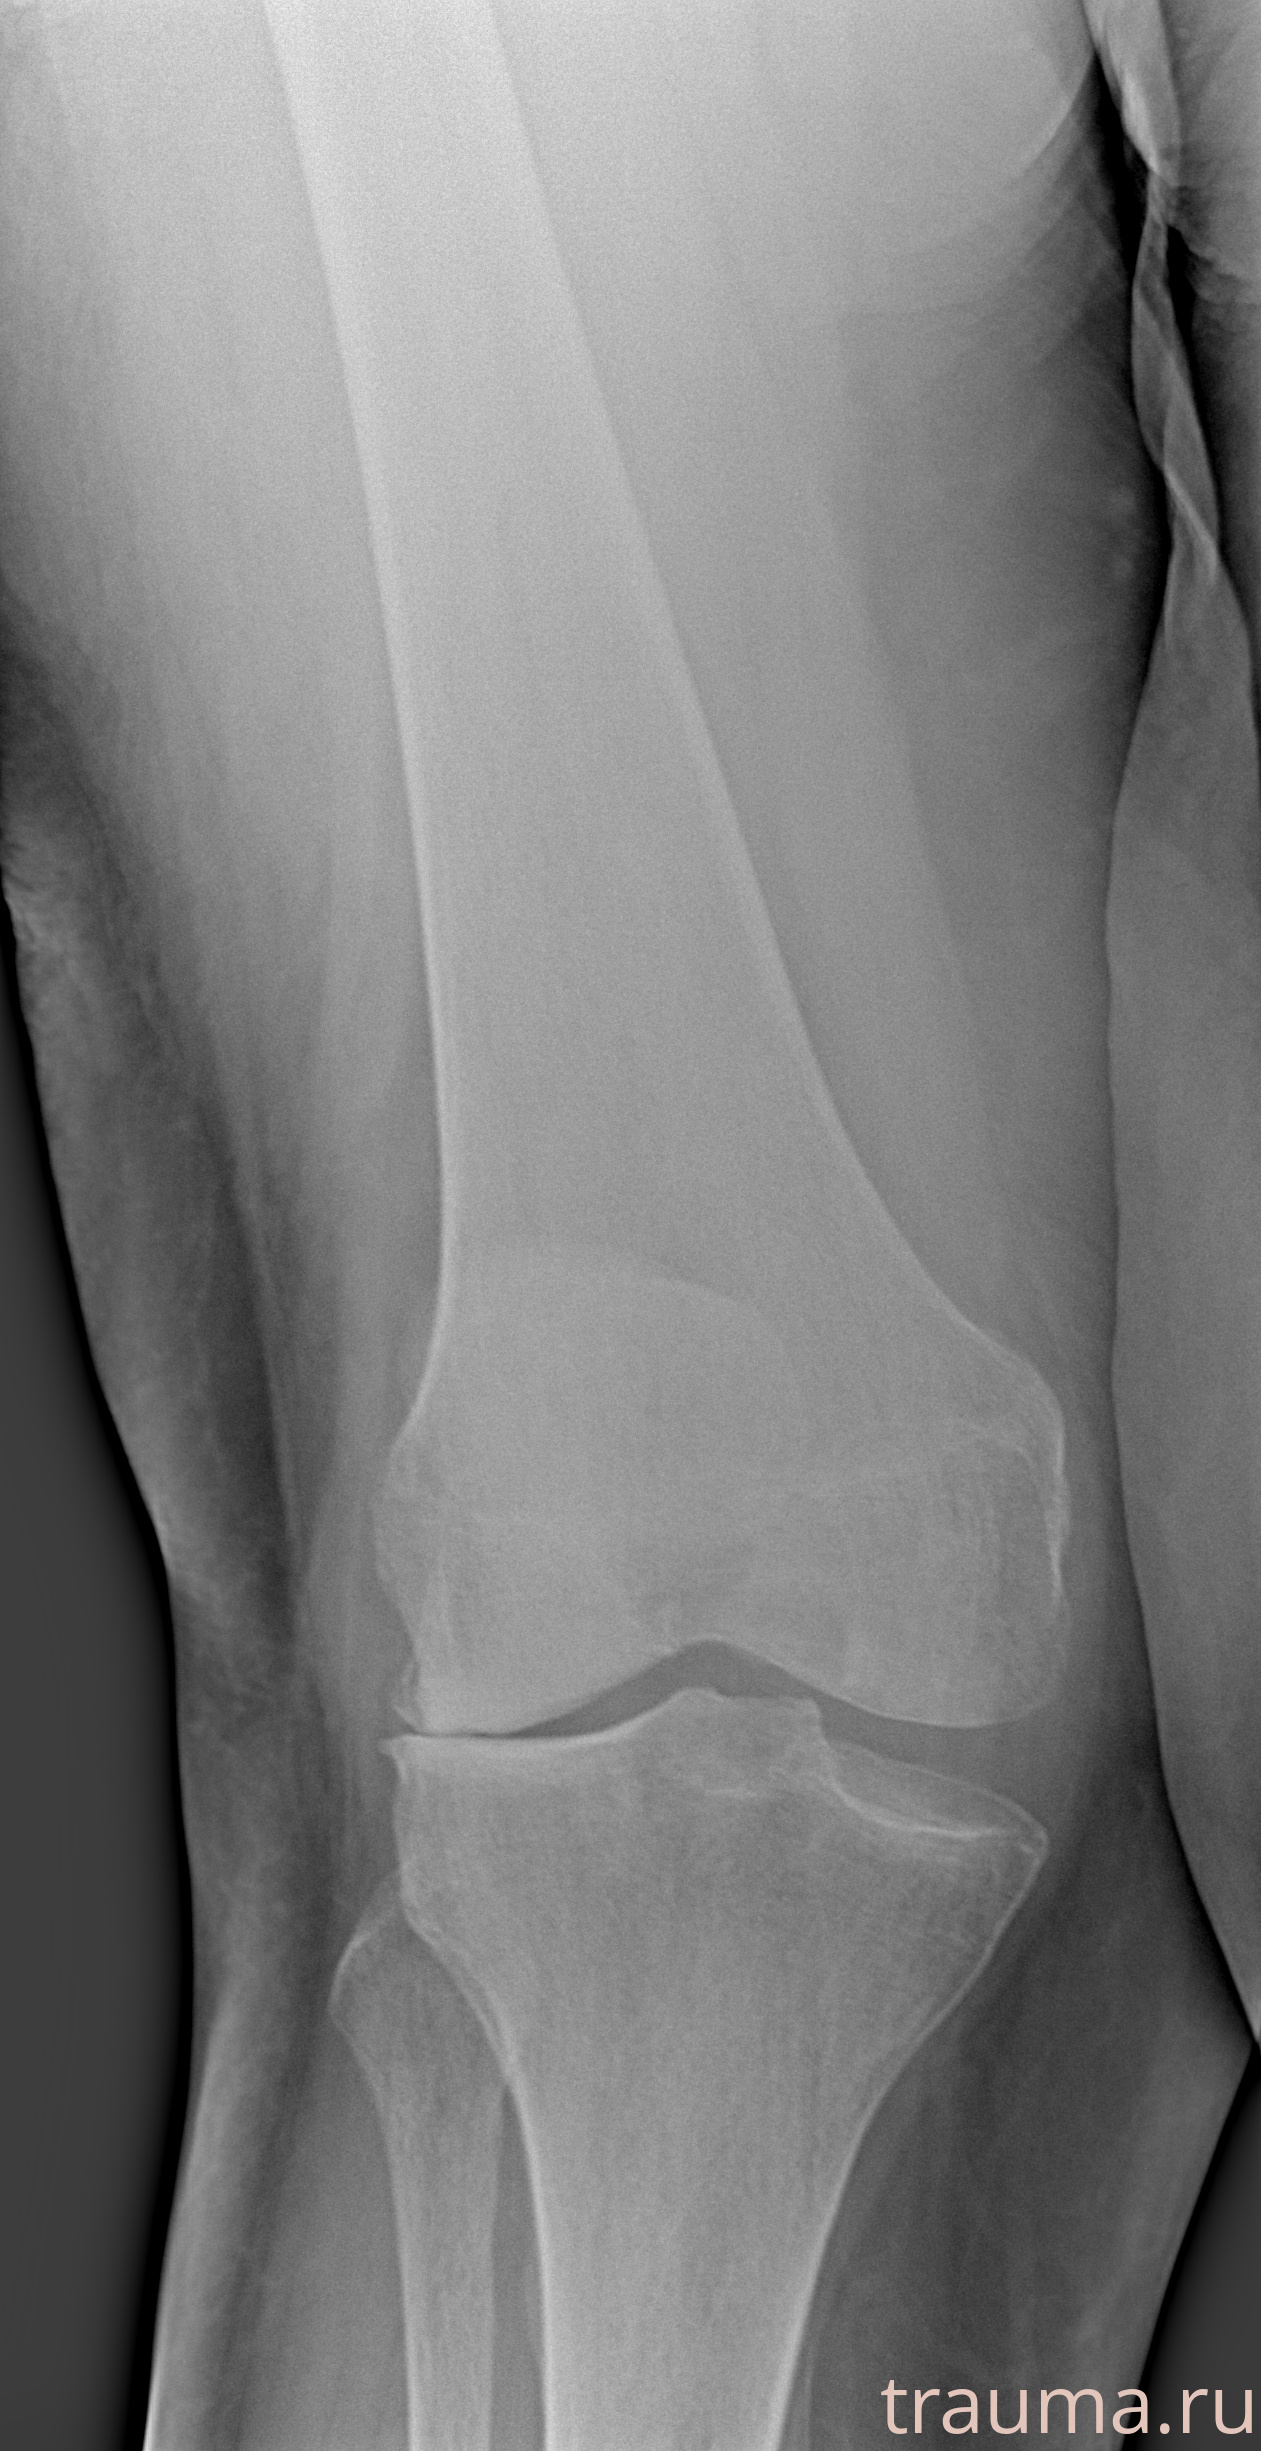

Рентгенограммы

Левая

Рентген на дому: по вашему адресу приезжает врач-рентгенолог, травматолог-ортопед с мобильным рентгеновским аппаратом, проводит диагностику травмы или заболевания, делает необходимые рентгенограммы, дает рекомендации по дальнейшему лечению. Получить качественные снимки в домашних условиях возможно благодаря уникальной методике, разработанной МосРентген Центром для института  Склифосовского